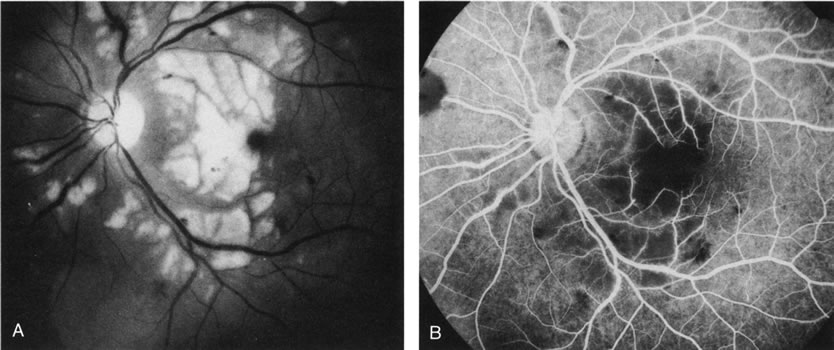

Clinically discernible peripheral dependent bullous neurosensory detachments have been described in patients with chronic CSC.85–92 Yannuzzi and co-workers first characterized the presence of RPE atrophic tracts extending inferiorly in the fundus periphery secondary to antecedent retinal detachment in patients with CSC.85 Presumably, there is a particularly severe and/or longstanding leakage of fluid from an RPE defect in the subretinal space at the posterior pole. The subretinal fluid gravitates inferiorly to form a dependent neurosensory detachment in a “flask,” “teardrop,” “dumbbell,” or “hourglass” pattern (Fig. 31). Sometimes the tract of subretinal fluid connecting the macular detachment with the bullous neurosensory detachment in the inferior hemisphere is so shallow that it is very difficult to appreciate. The RPE under the chronic retinal detachment experiences atrophic changes that appear as atrophic RPE tracts connecting the posterior pole with the dependent retinal detachment. The retina itself develops secondary manifestations including pigment migration, capillary dilatation (telangiectasia) proximally and capillary nonperfusion (ischemia) distally to the area of detached retina (see Fig. 31). The changes in the RPE consist of both RPE atrophy and pigment clumping in the form of perivascular deposits or bone spicules, a condition described by Gass as a “pseudoretinitis pigmentosa–like atypical CSC presentation.”87

Fig. 31. A 47-year-old woman with an18-year history of central serous chorioretinopathy in both eyes. A. Color photograph composite of the left eye shows bullous dependant detachment of the neurosensory retina inferiorly. B. Fluorescein angiogram composite reveals diffuse decompensation of the retinal pigment epithelium, multiple scattered pigment epithelium detachments 9PEDs), and obliteration of the retinal capillaries in the region of the detachments. Note the presence of early neovascularization at the junction between perfused and non-perfused retina. C. Clinical photograph of the left eye shows PED superior to the optic disc partially surrounded by fibrin deposits. D. Fluorescein angiography confirms the presence of active leakage from the serous PED. E, Color photograph composite of the same eye 2 months after laser treatment of the site of leakage reveals partial resolution of the detachment and lipid precipitation. F. Clinical photograph composite 16 months after the laser treatment in the area of the leakage shows complete resolution of the detachment and partial reperfusion of the inferior retina.